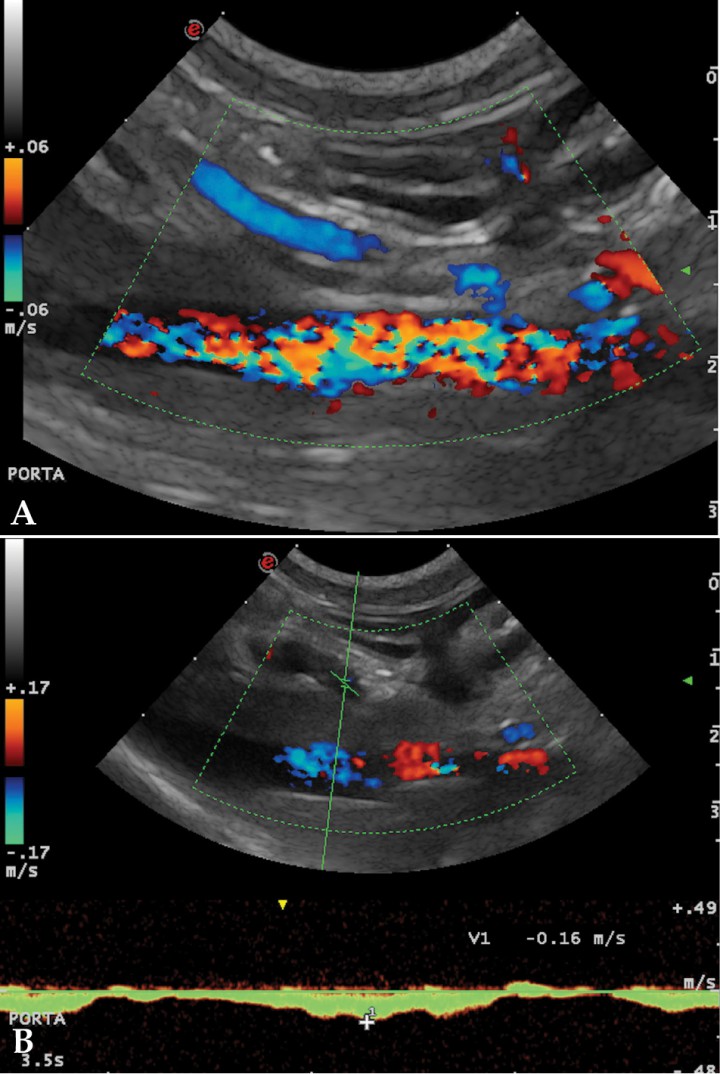

<p>(A) Corte longitudinal a nivel del hilio hepático. Doppler color. Vena porta con flujo hepatófugo. (B) Patrón del flujo portal con Doppler espectral. Ilustra el flujo de la vena porta en dirección hepatófuga y con la velocidad reducida.</p>

Figura 4

(A) Corte longitudinal a nivel del hilio hepático. Doppler color. Vena porta con flujo hepatófugo. (B) Patrón del flujo portal con Doppler espectral. Ilustra el flujo de la vena porta en dirección hepatófuga y con la velocidad reducida.

En nuestro paciente (Figs. 4, 5 y 7) la presencia de estos shunts múltiples, junto con el perfil de flujo portal y la presencia de ascitis, son altamente sugerentes de que el proceso de base está provocando HTP.